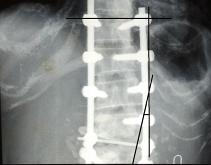

• 下肢行走困难14年,元凶竟是脂肪长在胸椎里

下肢行走困难14年,元凶竟是脂肪长在胸椎里

下肢行走困难14年,元凶竟是脂肪长在胸椎里 瑞康医院成功完成罕见胸椎肿物切除术 脂肪长在皮肤下很常见,但长在脊柱内则是罕见了。最近,一...

发布时间:2012-03-01 来源: